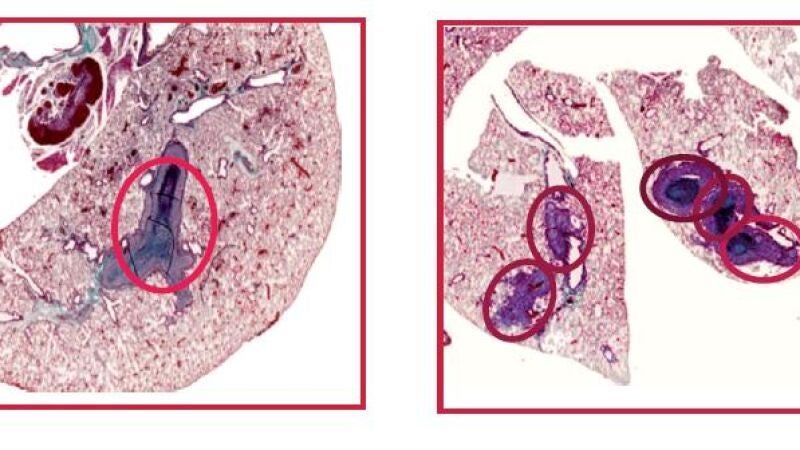

Ahora, un equipo de científicos españoles ha demostrado que, en ausencia de NCoR, los tumores adquieren mayor tamaño y son más invasivos. Los resultados, obtenidos mediante xenotransplantes en ratones inmunodeprimidos, han sido publicados en la revista PNAS.

“Los efectos observados en ausencia de NCoR se correlacionan con un aumento de la transcripción de un conjunto de genes prometastásicos que aumentan la malignidad de los tumores y disminuyen la supervivencia de los pacientes de cáncer”, afirma Ana Aranda, que dirigió el trabajo desde el Instituto de Investigaciones Biomédicas “Alberto Sols”, centro mixto UAM-CSIC.

El descubrimiento de NCoR ha resultado esencial para mediar los efectos antitumorales y antimetastásicos del receptor de hormonas tiroideas TRb; efectos que fueron descritos, en un trabajo previo, por el equipo que dirige Ana Aranda.

“La relevancia de estas observaciones para los tumores humanos se pone de manifiesto por el hecho de que la expresión de NCoR y TRb está reducida significativamente en los hepatocarcinomas y en los tumores de mama más agresivos”, señala la investigadora.